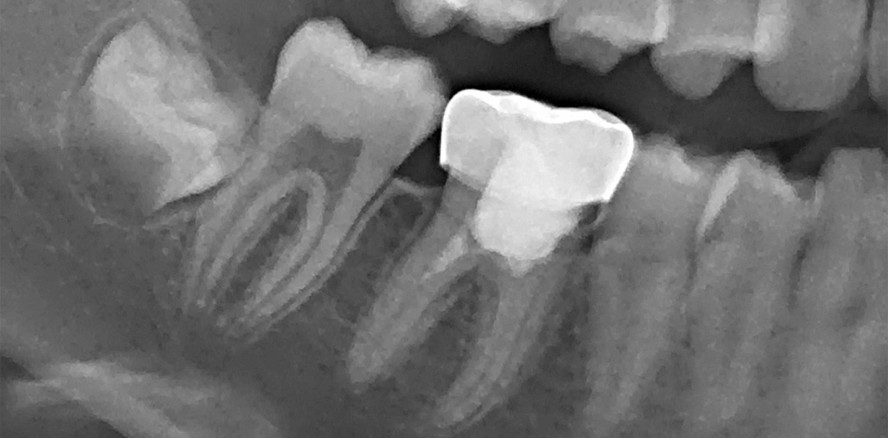

Nach klinischer Untersuchung erfolgte die radiologische Untersuchung: Im Röntgenbild war im Unterkiefer rechts am ersten permanenten Molaren eine tiefe kariöse approximale Läsion mit Pulpabeteiligung und einer wahrscheinlichen periapikalen Läsion (mesiale Wurzel) bei nicht abgeschlossenem Wurzelwachstum und dünnen Wurzelkanalwänden zu befunden (Abb. 2).